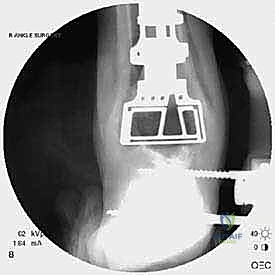

يتم تخدير المريض (نصفياً أو كلياً) واستخدام عاصبة (Tourniquet) لتقليل النزيف. يتم تعقيم الطرف السفلي وتجهيز أجهزة الأشعة المرئية (C-arm) داخل الغرفة.

الخطوة الثالثة: إزالة المفصل القديم (Explant Removal)

يتم استخراج المكونات المعدنية والبلاستيكية لمفصل (Agility) القديم بحرص بالغ للحفاظ على ما تبقى من العظم السليم.

الخطوة الخامسة: تركيب المفصل الجديد أو الدمج

يتم إدخال المفصل الجديد المخصص للمراجعة، والذي يحتوي غالباً على سيقان (Stems) تدخل عميقاً في عظمة الساق وعظمة الكاحل لضمان الثبات الميكانيكي. في حال وجود كسور في الكعب، يتم تثبيتها في هذه المرحلة.